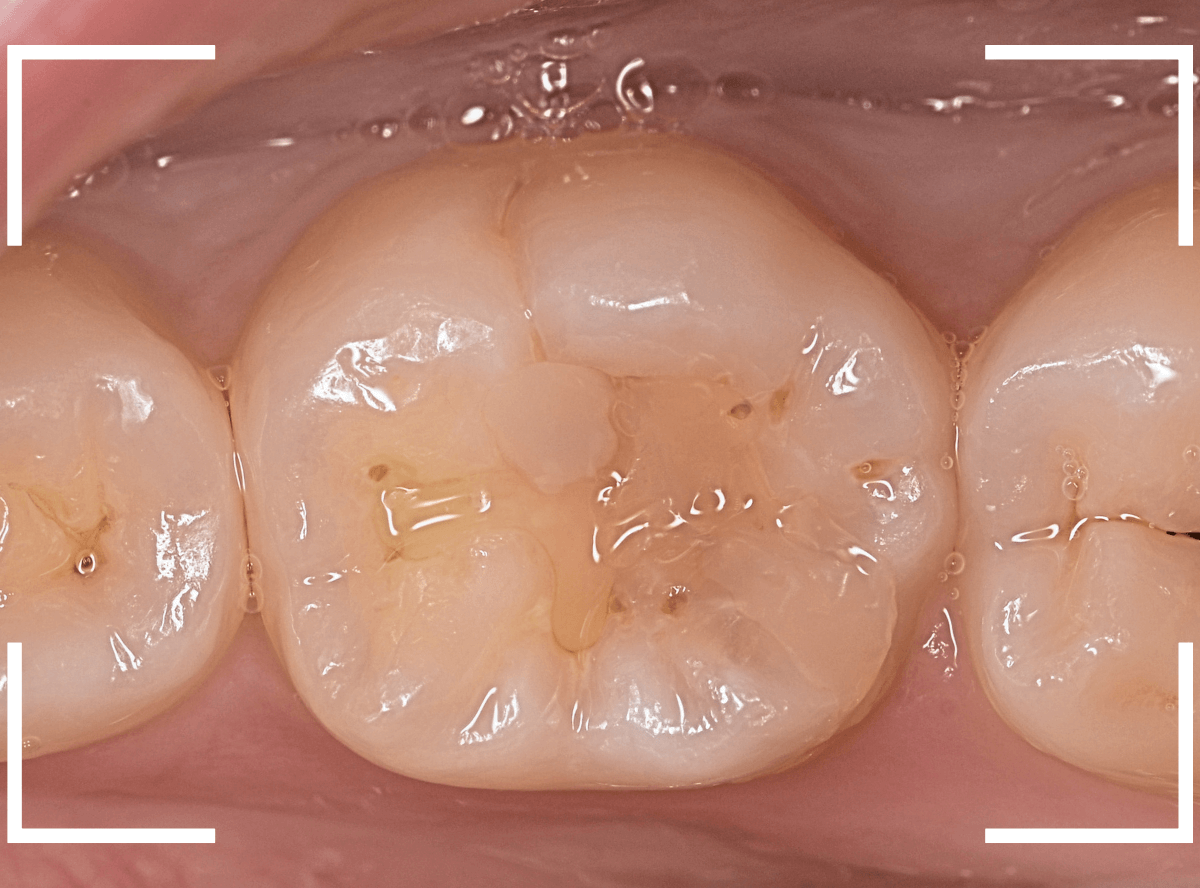

Case.17 レントゲンにはっきり写らないレジンの中の虫歯を削って調べる2

今回も、下の奥歯の虫歯を治療した例です。

特に症状はありませんが、以前に治療したレジンが劣化してすり減っているのと、少し中が黒く透けて見えて、虫歯になっているのが怪しいです。

青いラインが歯の神経です。

以前の虫歯が深めだったようで、レジンが深めにつめてあるのがわかります。

その下がうっすらと虫歯っぽい影になっています(赤いライン)。

虫歯になっているか微妙なラインですが、レジンも劣化していますので、患者さんにご説明して治療することになりました。

レントゲンで虫歯と思われる部分をレジンを除去しました。

見た目には虫歯かどうかはっきりわかりません。

う蝕検知液で染め出します。

うっすらと赤く染色されました。

レントゲン写真と同じく、レジンの下で静かに虫歯が進行し始めていたようです。

もともと深めの虫歯だった部分なので、早いうちに治療が進められてよかったです。

全てのレジンと虫歯を除去しました。

お薬をつめて、症状が出ないかしばらく経過観察します。

歯の外壁部分も薄くなってますので、レジンでは長期保存は難しいと思われます。

今回は、インレーで最終修復する予定です。